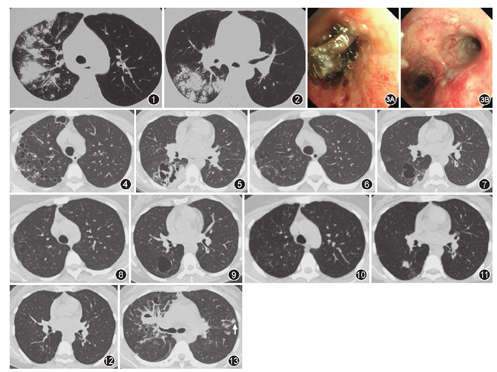

患者女,36岁,主因"发热、干咳、咽痛8 d,声音嘶哑、呼吸困难3 d"于2014年3月20日入院。患者入院前8 d劳累后出现发热,体温38.5 ℃,伴乏力、干咳、咽痛、肌肉酸痛,后体温逐渐升高到40 ℃,无头晕、头痛,无咳嗽、咳痰、胸闷、胸痛、心悸、大汗等不适。当地医院给予对症退热后体温可短时降至正常。4 d前就诊于当地市级医院,血常规示白细胞计数为6.17×109/L,中性粒细胞为0.84,胸部CT示双肺沿支气管分布的团片状、斑片状渗出影(图1,图2),诊断为肺部感染,给予静脉滴注阿奇霉素治疗。3 d前患者出现呼吸困难并逐渐加重,伴声音嘶哑,体温波动于39~40 ℃,就诊于我院急诊,动脉血气分析示(吸空气):pH值为7.47,PaO2为69 mmHg(1 mmHg=0.133 kPa),PaCO2为26 mmHg,给予莫西沙星400 mg/d(静脉滴注1 d后改为口服)4 d,患者体温仍于每日午后升高至39 ℃,伴轻度畏寒、寒战,余症状同前,遂收入院。既往体健。否认烟酒嗜好。入院体检:体温39.1 ℃,脉搏122次/min,呼吸频率35次/min,血压130/80 mmHg。呼吸急促,急性发热面容,意识清楚。呼吸困难,可见三凹征。双肺叩诊呈清音,双肺满布哮鸣音,以上肺为著,双下肺可闻及少量湿啰音,未闻及胸膜摩擦音。余未见异常。

入院第1天血常规示白细胞计数为11.0×109/L,中性粒细胞为0.88,血红蛋白为98 g/L,血小板计数为195×109/L,降钙素原为17.18 μg/L,ESR为104 mm/1 h,C反应蛋白为396 mg/L。给予静脉滴注莫西沙星、哌拉西林/舒巴坦,口服奥司他韦抗感染治疗。但患者入院当天喘憋进行性加重,给予甲泼尼龙40 mg静脉滴注及雾化解痉平喘治疗,效果不佳。患者逐渐出现谵妄伴二氧化碳潴留,查动脉血气分析(面罩8 L/min):pH值为7.098,PaCO2为80 mmHg,PaO2为118 mmHg,HCO3-为18.8 mmol/L,给予气管插管、呼吸机辅助通气,患者神智好转,生命体征好转。复查动脉血气分析患者酸中毒纠正,PaCO2下降至正常水平。第2天行支气管镜检查可见黏稠胶冻状分泌物堵塞多叶段支气管,使用可弯曲冷冻探头多次逐步取出,各叶段支气管黏膜广泛糜烂、触之易出血(图3)。第2天化验结果回报:支原体抗体IgM阳性,流感病毒A型及B型抗体IgM阳性;结核感染T细胞斑点试验阴性。

第3、5天再次出现气道阻塞,多次行支气管镜清理气道内分泌物及坏死组织,由于患者病情严重,在莫西沙星治疗基础上加用万古霉素治疗。痰培养、肺泡灌洗液培养、血培养结果回报均为甲氧西林敏感的金黄色葡萄球菌;患者体温、氧合指数、炎症指标等逐步好转,超声心动图未发现感染性心内膜炎,第7天拔除气管插管。第7天右主支气管黏膜病理回报为显著坏死、退变组织。第11天行胸部CT检查,右上叶及右下叶背段可见厚壁空洞,部分伴气液平面形成,同时可见多发小薄壁囊腔,左肺可见多发实性小结节(图4,图5)。

继续抗感染治疗1个月余,患者无发热、咳嗽等症状,出院后继续口服利奈唑胺1周,后换为头孢克洛口服1周,累计抗生素疗程2个月。随访患者2年,定期复查胸部CT,肺部病变逐步吸收,残留部分薄壁囊性病变,最后囊性病变亦完全吸收(图6~12)。

金黄色葡萄球菌为革兰阳性球菌,可通过两种途径引起肺炎:一为经支气管播散至肺内导致典型小叶性肺炎,另一途径为病原菌经血行播散至肺部引起肺内感染。两种方式均可引起双肺多发性化脓性病变,并为严重感染导致组织严重破坏形成肺脓肿、肺囊样病变,但影像学表现并不相同,经支气管播散引起肺脓肿面积大,病变多靠中心,影像学为典型肺脓肿表现。血行播散的肺脓肿又称为脓毒性肺栓塞(Septic pulmonary embolism,SPE)[1],肺内表现为多发的胸膜下厚壁小空洞、结节,有时其内部分可见滋养血管征。滋养血管征定义为一支血管影直接连接结节中心(图13),此征象高度提示考虑SPE[2,3,4],但也可见于肿瘤血行肺转移[5]。患者起病时影像学为典型小叶性肺炎,后很快出现肺内带的厚壁大空洞,及胸膜下厚壁小空洞,炎症好转过程中遗留弥漫分布的囊腔,病变主要是肺脓肿引起肺炎症破坏后遗留腔,SPE未残留明显腔,肺内病变长期随诊,可见绝大部分囊腔逐步吸收。

影像学随访:患者右肺病变重,治疗后8周后胸部CT可见部分囊腔明显吸收,但原来较大的脓肿吸收慢,尤其是右肺上叶及右肺下叶背段部位(图6)。8个月胸部CT可见其余囊腔基本吸收,右肺上叶囊腔进一步变小,右肺下叶背段仍残留囊腔(图8),19个月后胸部CT见右肺下叶背段残留囊腔闭合,残留实变及索条影(图10)。